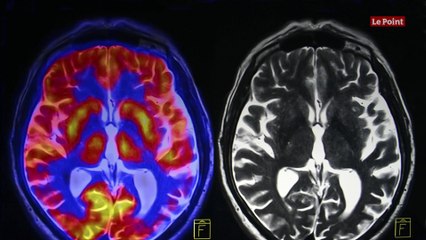

Après la mort, des cellules du cerveau restent fonctionnelles pendant 48 heures. Le docteur Ed Lein, un scientifique américain, espère faire avancer la recherche en utilisant des parties vivantes du cerveau, explique la BBC. C'est un peu fou que nous ayons un champ si vaste où nous essayons de résoudre les maladies du cerveau et qu'il y ait très peu de compréhension du cerveau humain lui-même. , Le docteur Ed Lein, lors d'une réunion de l'American Association for the Advancement of Science, à Seattle. Pour mieux comprendre cet organe complexe, lui et son équipe récupèrent des tissus provenant de cerveaux humains, avec l'accord des personnes, à l'issue d'opérations chirurgicales. Certaines cellules continuant de fonctionner jusqu'à 48 heures après la mort, c'est une course contre la montre qui s'engage alors pour les récupérer et mener des recherches dessus. Pour Ed Lein, il faut néanmoins passer par cette étape pour espérer trouver des traitements plus efficaces contre des maladies du cerveau, comme celles d'Alzheimer ou de Parkinson. Les scientifiques utilisent des parties vivantes du cerveau humain pour leurs recherches depuis plusieurs décennies, mais nombreux sont ceux qui privilégient les études sur les cerveaux des rongeurs, relaye inews. Sauf que les différences entre les cerveaux humains et ceux des souris ou des rats sont trop importantes, selon Ed Lein. Le scientifique ajoute auprès de la BBC que le cerveau de la souris est « mille fois plus petit » que celui d'un humain.